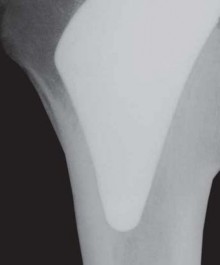

The Tapered Stem Cementless fixation in total hip arthroplasty emerged as a result of the perceived need for …